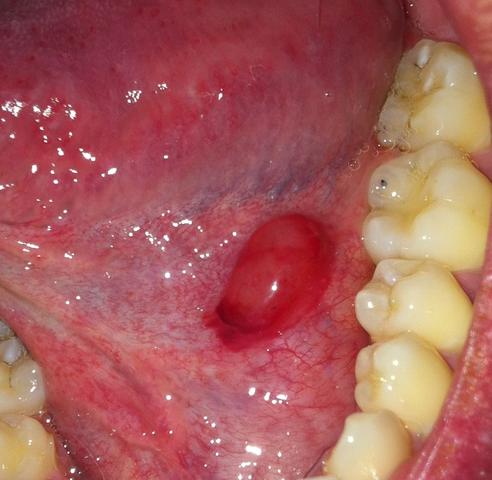

Froschleingeschwulst Ranula Ursachen Therapie Prognose

Was Ist Eine Ranula Und Wie Kann Sie Behandelt Werden Wefix